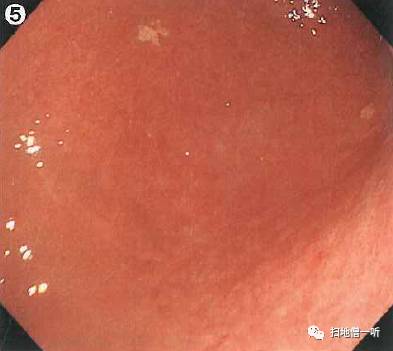

【5】

Q:胃癌在何处?

提示:请注意单发糜烂

A:胃癌在图1。HP未感染胃癌。

背景粘膜光滑而有光泽,呈现均一的橘红色粘膜像,胃底腺区域RAC阳性,存在胃底腺息肉,以上均提示HP未感染。幽门前区大弯侧可见单发糜烂伴血痂附着,此病变为重点观察处。HP阴性的幽门前区经常会见到此类多发糜烂灶,故与癌的鉴别非常困难,鉴于此病例糜烂为单发,故需要进一步观察。

靛胭脂喷洒后病变中央可见边界清晰的小凹陷面,因良性炎性糜烂常常表现为周边平缓的移行。染色后征象怀疑癌,但仍不能以此确诊,故需进一步行活检。

最终病理诊断:

幽门前区大弯,O-IIc,4mm,sig,T1a (M),UL(-)

小结:单发糜烂需与癌鉴别

进一步需靛胭脂染色